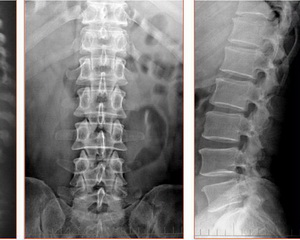

椎间盘存在与脊柱的两个椎体之间,所以不光在腰椎之间有椎间盘,在颈椎、胸椎之间同样也有椎间盘;有些拍过脊柱X光的人可能会质疑了,“我怎么在片子上看两个椎体之间什么也没有?”

确实,在片子上看,两个椎体之间什么也看不到,但是看不到不代表它就不存在。

这是因为椎间盘属于软组织,在X光下不显影,所以你看不到,但是通过CT或者MRI检查就能看到椎间盘了,这也就是为什么好多腰痛的病人,在怀疑是腰椎间盘突出症的情况下,要做CT或者MRI检查而不是简单的拍个片子!